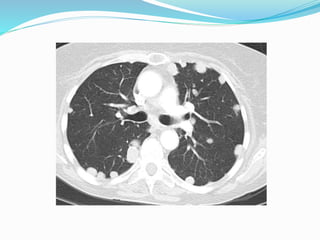

 HRCT

 Nodular thickening of the interlobular septa and

thickening of the centrilobular bronchovascular

bundles.

Cont…  HRCT  Nodularthickening of the interlobular septa and thickening of the centrilobular bronchovascular bundles.